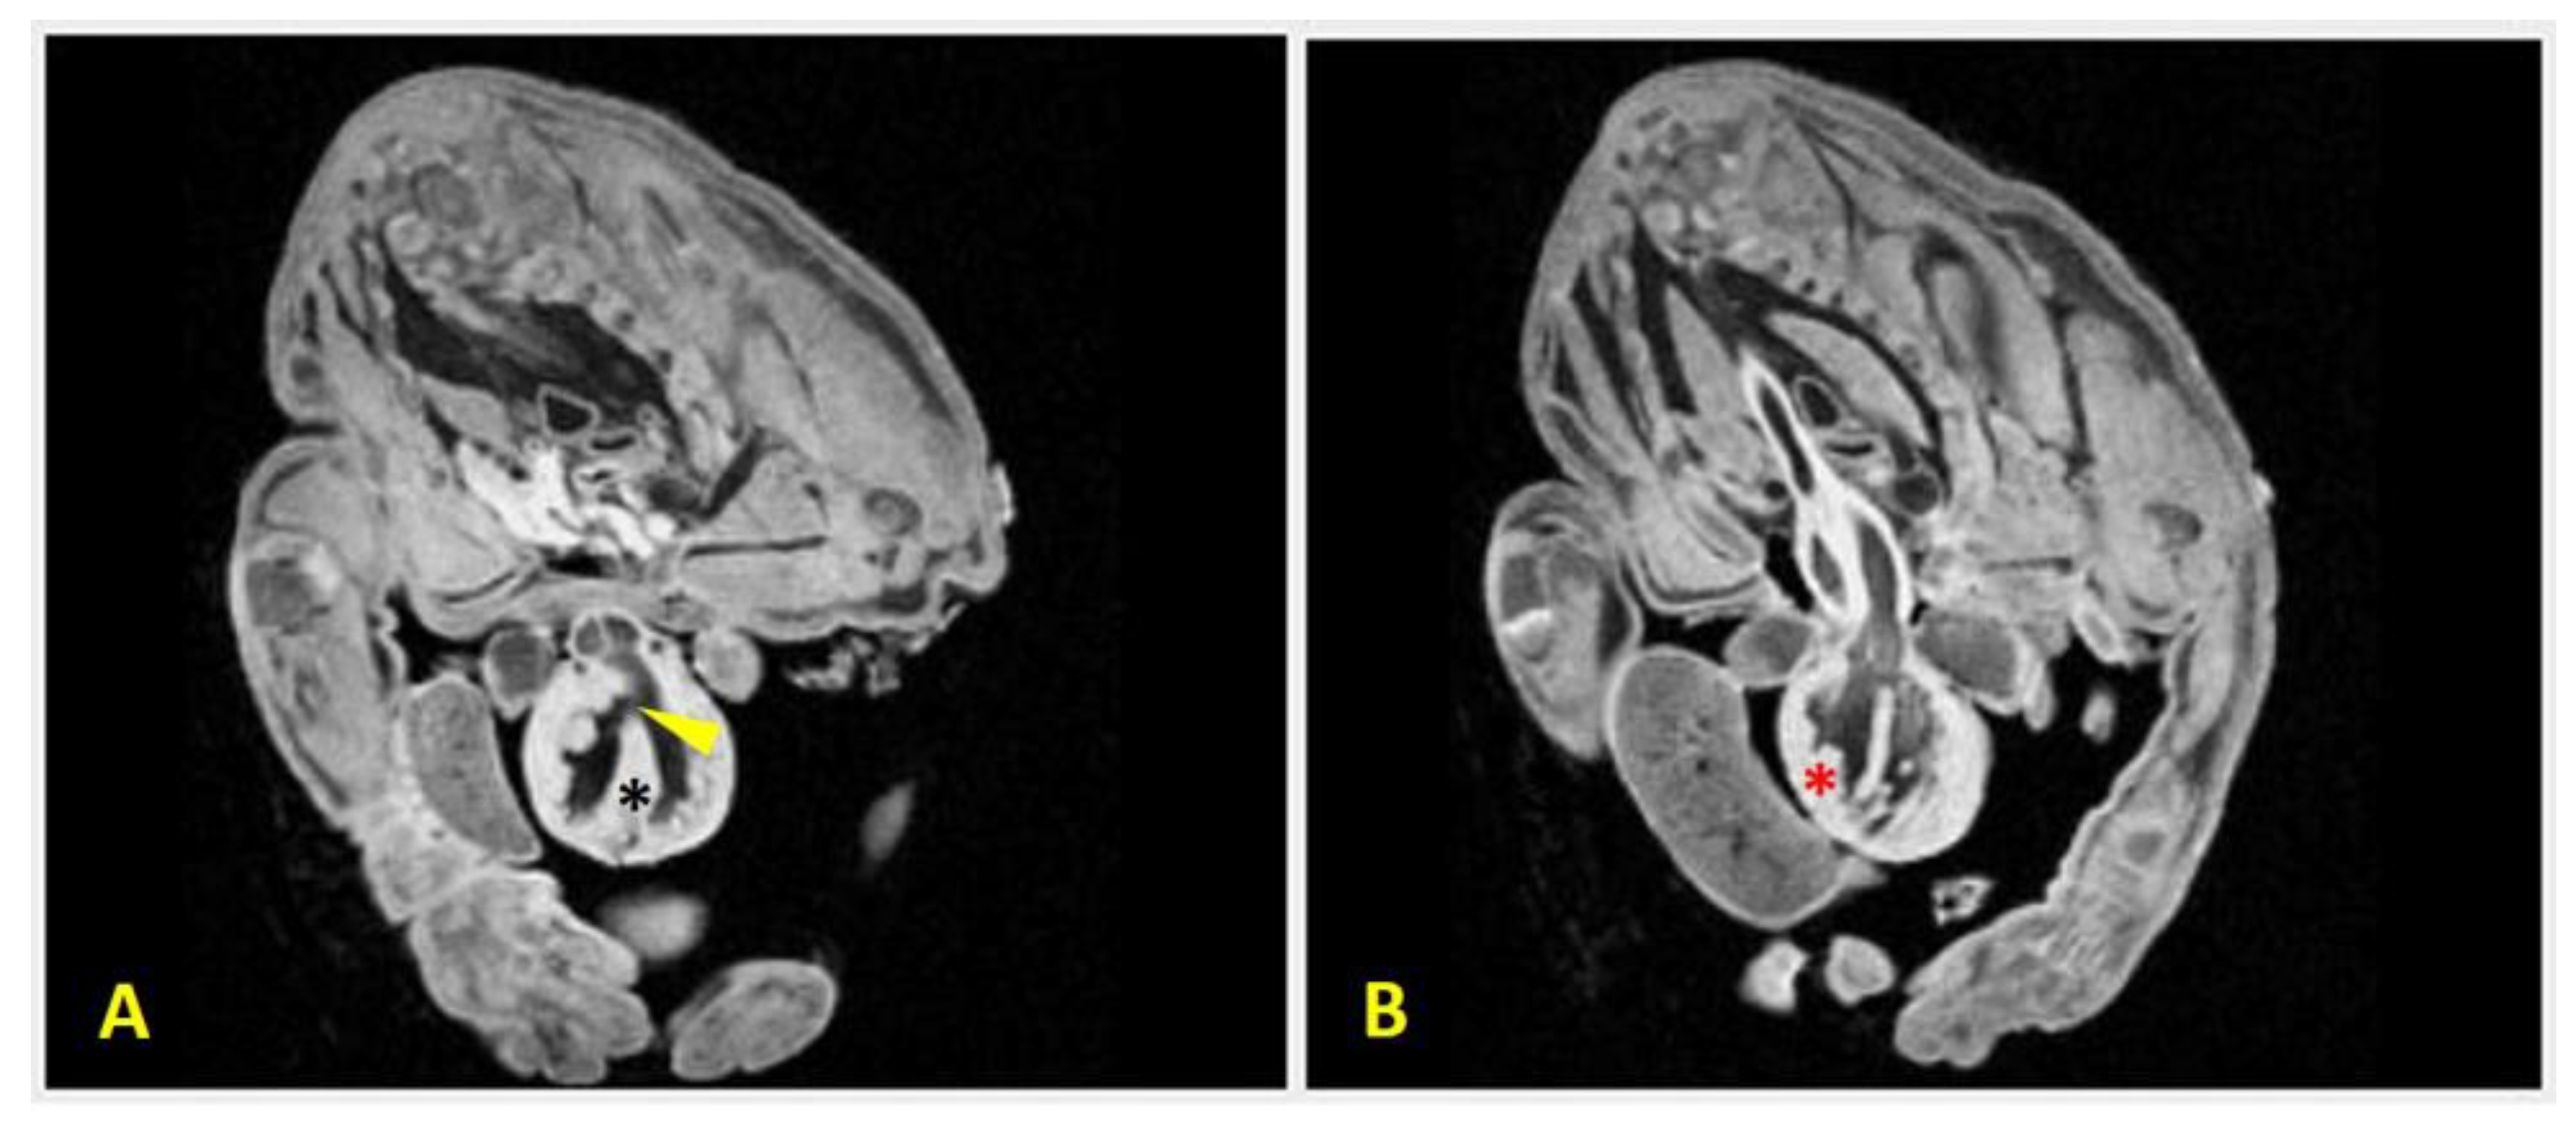

Figure 8. MRI scans of Case 2 (male Chihuahua) demonstrating congenital cardiac anomalies. Two transversal sections of the MRI scan reveal:(A) a ventricular septal defect (arrowhead), which is visible as a discontinuity in the interventricular septum (black asterisk), allowing communication between the ventricles; and (B) right ventricular hypertrophy which is evidenced by thickening of the right ventricular wall (red asterisk). These findings support the diagnosis of complex structural heart malformations associated with body wall defects.